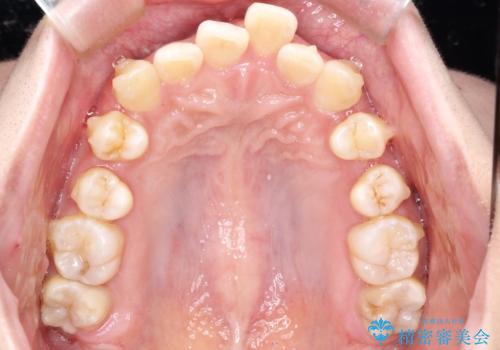

重度のガタガタのインビザラインによる非抜歯矯正

- 全体的なガタガタを気にされて来院されました。

抜歯矯正も考えられる状態でしたが、ご本人的になるべく歯を抜かない矯正を希望されました。

奥歯を後方に移動させるのと、歯と歯の間にわずかに隙間を作ることでスペースを確保して、抜歯をせず歯を並べる計画としました。

ガタガタの度合いが大きかったので少し時間がかかりましたが、非常に協力的な患者様でしたので、抜歯をせず計画通りに治療を終えることができました。